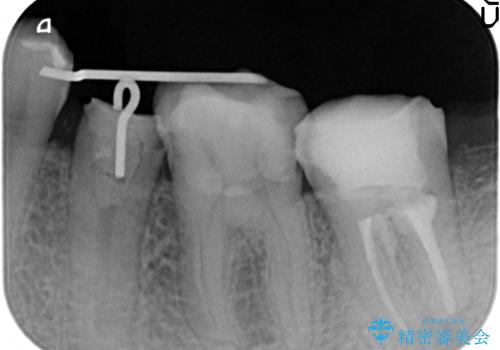

痛みの原因は6番目の虫歯であること、5番目、6番目の歯は歯茎より深い虫歯であり現状では保存が難しいことを説明した上で、歯を挺出させる部分矯正と歯茎を下げる歯周外科を行いました。

手術後歯茎の治癒を待ち、オールセラミッククラウンによる補綴を行いました。